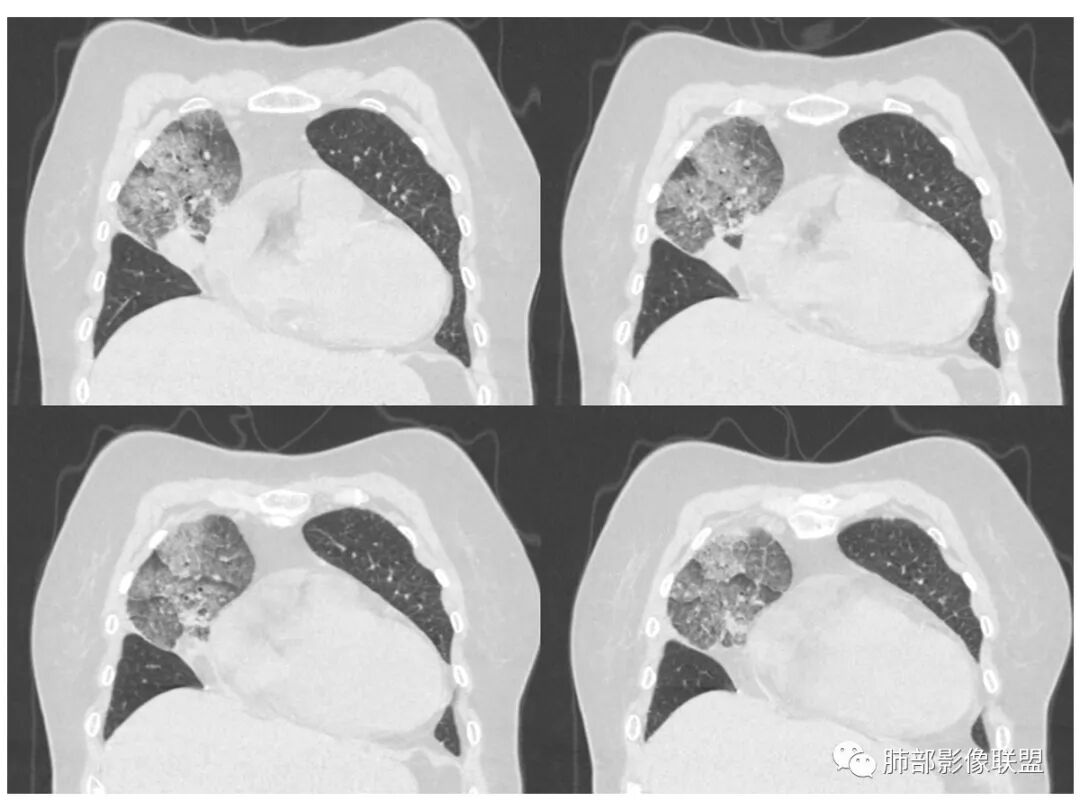

右肺上叶大片状阴影,内见僵硬的支气管,部分支气管轻度扩张,内见一空洞和液平,病灶边缘可见磨玻璃影,首先考虑恶性病变,粘液性腺癌伴感染可能。

老年女性,慢性病史,白色痰液,量多,病灶起于胸膜下,实性加磨玻璃,磨玻璃边缘偏轻,跨叶生长,病灶内可见枯树枝,考虑肺炎型肺癌。

老年女性,右肺上叶大片实变及磨玻璃密度影,磨玻璃边缘清晰,内可见小叶间隔增厚,内可见空洞,似可见分隔,叶间裂局部膨隆,纵膈窗,没有增强,枯树枝不明显,肺炎型肺癌可能,鉴别大叶性肺炎,结核?

胸CT:右肺上叶实变内可见支气管充气征,近端支气管狭窄,远端扩张,周围可见毛玻璃影,右肺中叶支气管闭塞,并可见气道壁钙化,右肺中叶体积缩小,实变内可见空洞,并可见气液平面,空洞周围可见毛玻璃样影,右肺下叶支气管开口狭窄,右肺门淋巴结肿大。纵隔窗可见病灶与壁层胸膜间隙增宽,考虑良性病变-----感染性病变------TB?

老年女性,右肺中上叶病灶,血象不高,血沉高,TB dna阴性,上叶尖端病灶,紧贴胸膜,边界似清非清,中间可见实变,内见枯树枝征,首先考虑粘液腺癌可能性大。患者右肺中叶见空洞、气液平,病灶没多发空洞,可见气液平,考虑合并TB感染。

老年女性,无诱因咳嗽咳痰,白色粘液痰,抗炎治疗无好转,右肺多叶磨玻璃影,其内见枯树枝征,磨玻璃边界清,中间见实变影,且部分实变影内见空洞或局部支气管扩张,内壁光整,无纵隔淋巴结肿大,常规考虑粘液性腺癌,感染性病变待排,细菌性的排除,白细胞不高,不太支持,建议支气管镜检。

1.右上肺大片状影,周围有磨玻璃影,支气管截断征、枯枝征、远端支气管充气征,可见多个大小不等囊泡(支气管阻塞活瓣作用形成),病灶有少许收缩力感,叶间裂被稍牵拉内移;

病史老年女,白痰;影像实变,ggo多数边界清,病灶下缘部分不清,枯树枝,支气管近端阻塞、僵硬,病灶跨叶;病灶内空洞,有液平;间质增厚有结节感;肺炎型肺癌大于干酪性肺炎。

老年女性,慢性病程,咳嗽伴白色粘液痰,无发热腹痛,糖尿病,白细胞及C反应蛋白不高,血沉快,铁蛋白高。胸部CT,右肺上叶大片状实变伴磨玻璃密度影,边界不清,边缘局部膨隆,叶裂弧形下坠,实变影宽基底与胸膜相贴;右肺下叶前基底段见类似病灶;右肺中叶不张并空洞形成,空洞内见气液平面;综合考虑右肺上叶及下叶肺炎型肺癌,右肺中叶结核。

老年女性,病史1月,右肺上中叶大片状影,跨叶,上叶为主,磨玻璃为主,边界模糊,部分实变,内见空洞影和液气平面,壁光滑,支气管开口狭窄,局部有扩张,右肺门淋巴结钙化,首先考虑感染性病变,结核可能,鉴别粘液腺癌。

老年女性,亚急性起病,右肺上中叶大片状影,跨叶,上叶为主,磨玻璃为主,边界模糊,部分实变,内见空洞影和液气平面,壁光滑,洞内可见结节形成,局部有扩张,首先考虑感染性病变,结核可能;洞内可见结节样病灶,鉴别合并曲霉、肿瘤。

薄厚不均匀,枯树枝,支气管壁僵直,叶间裂膨隆,白色粘液痰,肿瘤标志物增高,考虑粘液肺癌可能。

患者老年女性,亚急性起病,胸部CT:右肺上叶大片实变,可内见坏死性空洞,可见mGGO,GGO边缘清晰,局部彭隆,内见支气管充气征,可惜没增强,粘液腺癌要考虑,但病灶明显是内朝外不支持,综合考虑结核,建议查痰找抗酸杆菌、气管镜

老年女性,咳白色粘液痰,右肺跨叶大片高密度影,密度不均匀,其内见支气管枯树征,有空洞,边缘部分清楚,叶间裂有下坠膨隆感。考虑粘液腺癌,鉴别干酪性肺炎

实变区像支气管爬行征?空洞区也有钙化和边界清楚模玻璃影

以前老师们也讲过边界清楚的模玻璃影及反晕征注意TB

2.南大理论:粘液腺癌起源于外周,所以主体病灶位于胸膜下多见,这个病人主体病灶位于中心,外周磨玻璃为主,部分磨玻璃模糊

3.熊老师告诉我们:肺结核可以有磨玻璃,这个我以前一直不知道,右肺门淋巴结有钙化,病灶内纵膈窗隐约细细点状钙化,所以结核磨玻璃可以,

这个病人可以当做干酪性肺炎的扩大延长版